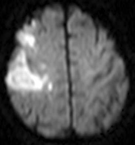

脳卒中には原因があります。その原因がコントロールできなければ高い確率で再発します。原因を調べるために、検査をします。血液検査、心電図、レントゲン、エコー、CT、MRI、脳血管造影、SPECT等。原因がみつかったら、それに応じた治療を行います。

脳梗塞の症状を劇的に良くする可能性がある薬(点滴)です。ただし、脳梗塞発症4.5時間以内しか使えません。血管がつまると脳細胞が死に、麻痺等の症状があらわれます。太い血管がつまればより多くの脳細胞が死に、より強い症状があらわれます。しかし急につまった太い脳血管を脳細胞が死滅する(脳梗塞に陥る)前に再開通させれば、症状が劇的に良くなる可能性があります。 t-PA(組織プラスミノーゲンアクチベーター、一般名をアルテプラーゼ)という薬剤を点滴し、血管につまっている血の固まりを溶かすことで血管を再開通させます。必ず発症4.5時間以内に点滴開始しなければなりません。病院に着いてから、血液検査やCT等を終わらせなければならないので、発症したらすぐに病院受診しないと間に合いません。ただし4.5時間以内でも、すでに脳梗塞が完成している患者さまには使えません 。